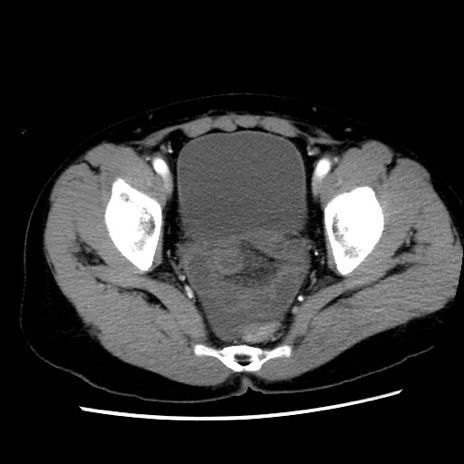

矢状断像

【症例】 50歳代女性

【主訴】 腹痛

【現病歴】前日生レバーを食べた。今朝に排便あり。 昼前に突然発症の腹痛を生じ、当院救急外来を受診した。

【既往歴】 子宮筋腫にてで子宮全摘後

【身体所見】 意識清明、腹部:平坦、軟、下腹部やや左を中心に圧痛・反跳痛あり、筋性防御あり

【データ】WBC 7800、CRP 0.07